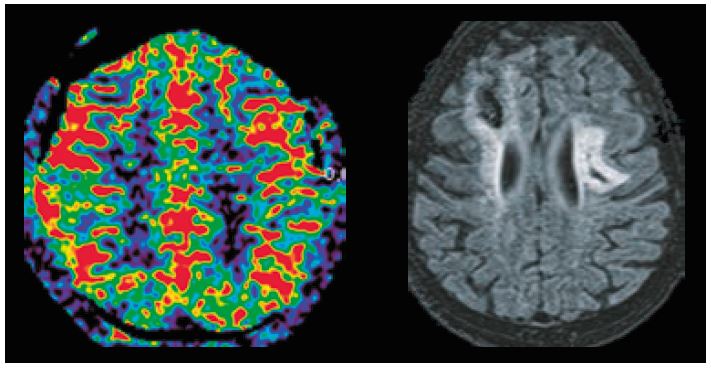

На рисунку 4 показана однобічна лівостороння лобова полімікрогірія у пацієнта чоловічої статі з епілепсією. Осьовий 3D MPRAGE MPR показує багато складок (звивин). Об’ємні зображення показують аномальні звивини.

Рис. 4. Показані невеликі складки на аксіальних зображеннях MPRAGE (угорі), зниклі звивини під час рендерингу об’єму (внизу ліворуч і посередині) та аномальні ділянки волокон білої речовини на DTI (унизу праворуч).

Полімікрогірія характеризується як аномальний розвиток головного мозку до народження, а розвиток дрібних і багатьох складок може бути причиною такого неврологічного розладу, як епілепсія.

ПЕТ-КТ – це одне з обстежень, яке можна виконати для виявлення аномалій перфузії, які можуть свідчити про метаболічні та функціональні аномалії. У цих випадках перфузія ASL є хорошою альтернативою, яка є неінвазивною, не вимагає опромінення та її легко запланувати за стандартним протоколом. На рисунку 4 показано на картах церебрального кровотоку дефекти перфузії на лівій лобовій стороні, які можна співвіднести з аномальними складками в цій області.